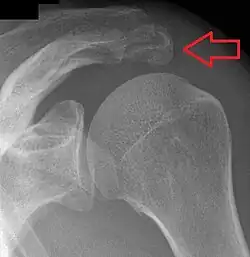

Épaule

.jpg)

Un os acromial se forme lorsque l'un de ses quatre centres d'ossification ne parvient pas à fusionner. Ces quatre centres d'ossification sont appelés de la pointe à la base pré-acromion, méso-acromion, méta-acromion et basi-acromion. Dans la plupart des cas, les trois premiers fusionnent entre 15 et 18 ans, tandis que la partie de base fusionne avec la colonne scapulaire à 12 ans. Un tel échec de fusion se produit dans 1 à 15 % des cas[15],[16]. Cela provoque rarement une douleur.